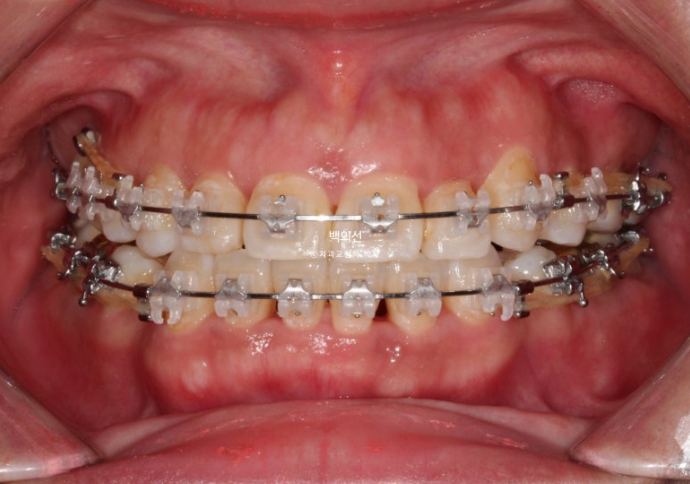

2년후인 23년 11월 모습입니다.

23.11

발치공간이 약 3mm씩 남아있습니다.

잘라낸 브릿지의 지대치는 임시치아 상태로 교정을 진행하고 교정치료 마무리 시점에서 새 크라운으로 최종 수복을 합니다.